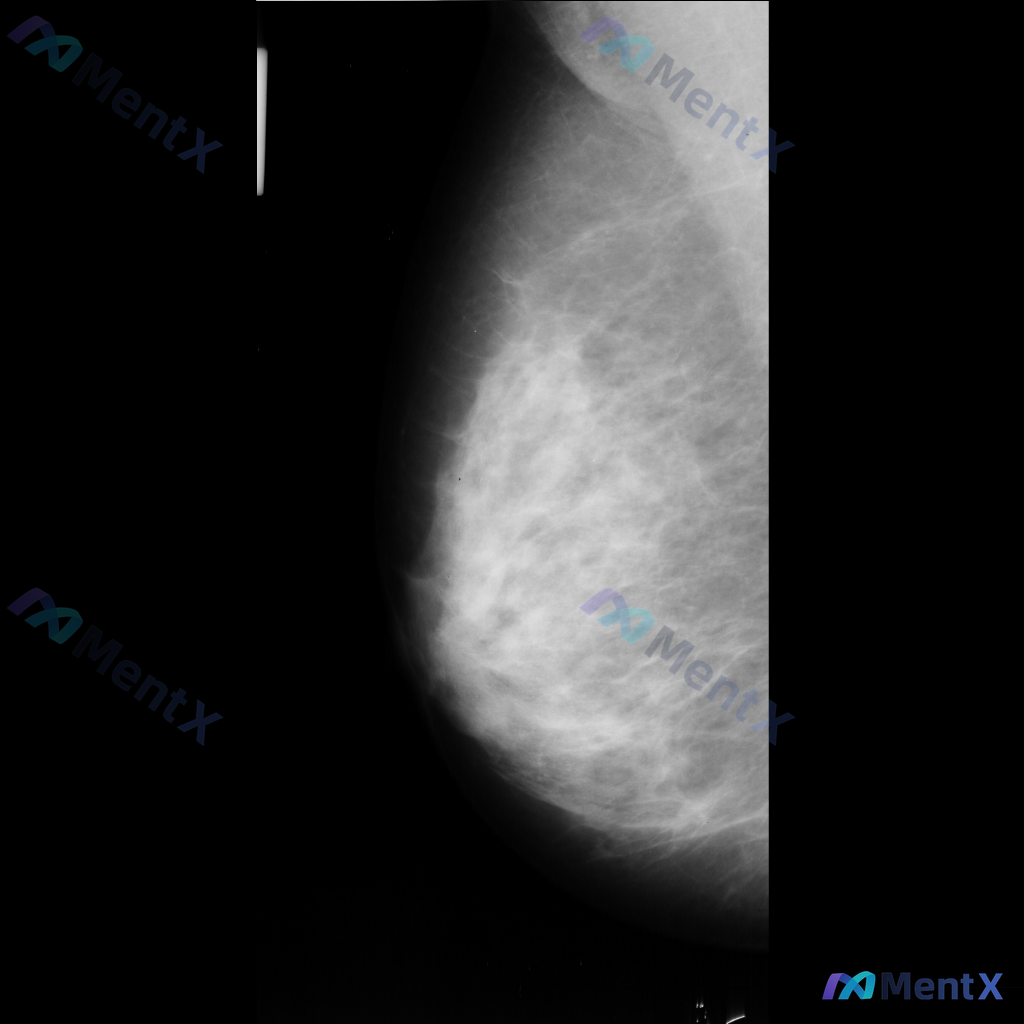

整理到一张单侧乳腺钼靶影像的相关描述,分享给大家讨论: - 乳腺背景:腺体组织呈不均匀致密型,脂肪与腺体交错分布 - 主要异常:影像中央偏下方可见一区域性致密影,边界模糊,与周围腺体融合,性质待查 - 其他征象:提及可见散在的、数量极少的细小点状钙化,但无法详细描述形态和分布 目前只有这一张单侧片的...

整理到一份乳腺钼靶的影像描述资料,想和大家讨论一下读片思路。 基本情况: - 图像显示为不均匀致密型乳腺 - 主要异常:乳腺中部区域可见片状致密影,与周围腺体组织相融合,边界不清晰 - 目前仅为单侧乳腺图像,无法进行双侧对比 - 影像中未发现明确的边界清晰或不规则形态肿块、可疑钙化、结构扭曲、皮肤增...

整理到一张乳腺钼靶影像的分析资料,大家可以先基于现有信息讨论一下。 基本影像学表现 - 可见形态不规则的致密区域,伴有结构扭曲和模糊边缘 - 背景乳腺腺体呈 BI-RADS B/C 型(致密性增加) 目前从影像上看,存在几种可能的方向,想听听大家的第一判断:单看这组影像学表现,你会先考虑哪一种异常方...